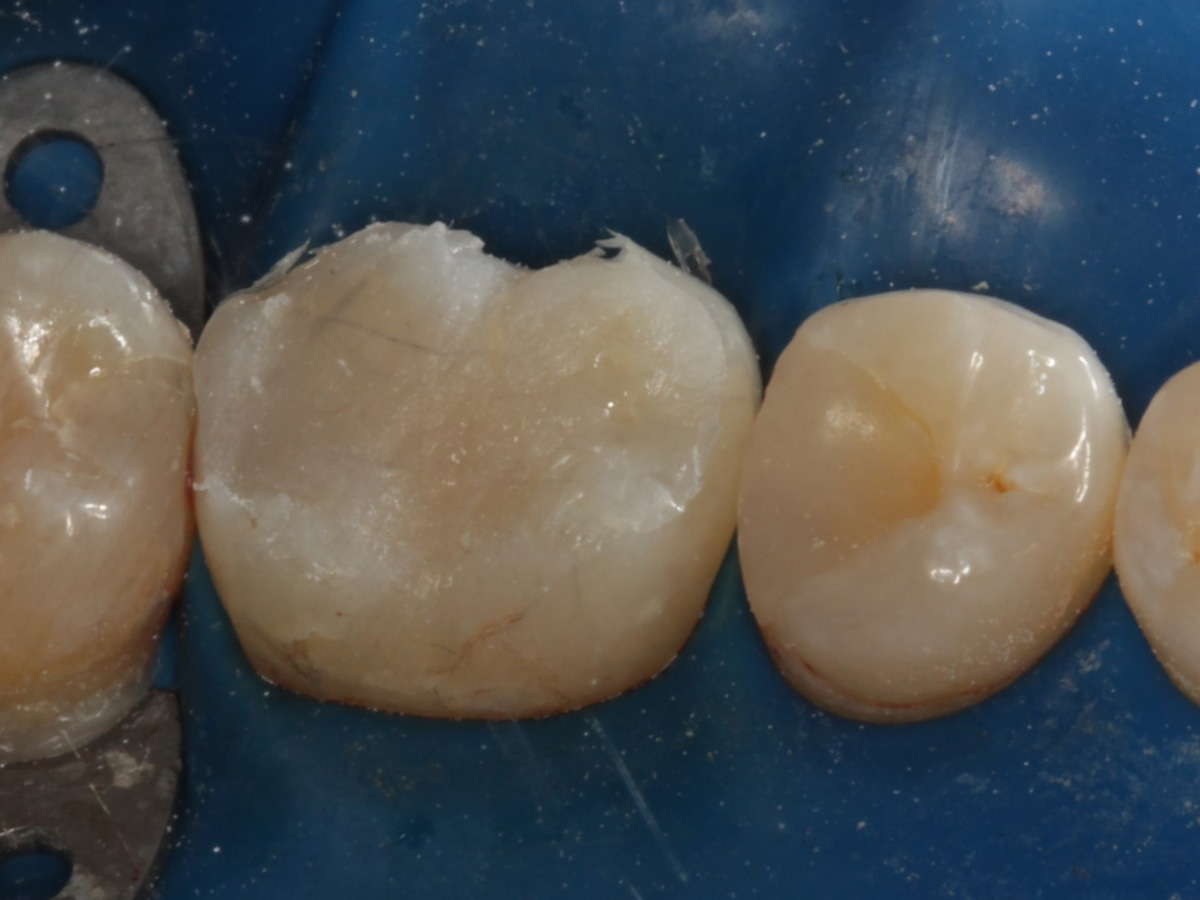

Abbildung 1

Intakte Kaufläche bei Approximalraumkaries an Zahn 36 mesial und distal